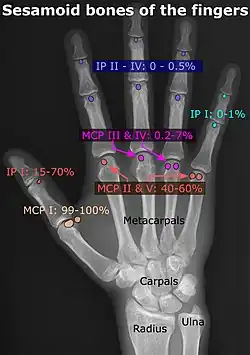

- ↑

- Location and structure: Erica Chu, Donald Resnick (June 2014). "MRI Web Clinic — June 2014: Sesamoid Bones: Normal and Abnormal". Radsource: PACS Radiology Systems. Retrieved 2017-11-04.